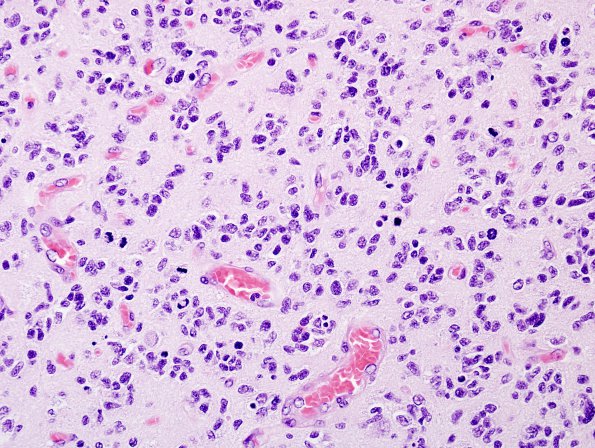

Washington University Experience | NEOPLASMS (GLIAL) | Glioblastoma, small cell type | 4A3 GBM , small cell features (Case 4) H&E 2.jpg

Higher magnification shows the cytologic features of the majority of the tumor cells (H&E). ---- In light of the histologic appearance suggestive of small cell glioblastoma, FISH probes were also employed to investigate the status of the EGFR gene (probes to EGFR, 7p12, and CEP7, the chromosome 7 centromere) and the long arm of chromosome 10 (probes to DMBT1, 10q25-26, and PTEN, 10q23.3). In this case, there was no codeletion of 1p19q; rather, there were normal dosages (i.e., two copies) of chromosome 1 with trisomy of chromosome 19. In addition to trisomy of chromosome 7, there was superimposed amplification of the EGFR gene. The added finding of 10q deletion here is in keeping with a diagnosis of small cell glioblastoma. ---- Comment: Although not pure, the overall histology and FISH results support the diagnosis of glioblastoma with focal small cell features